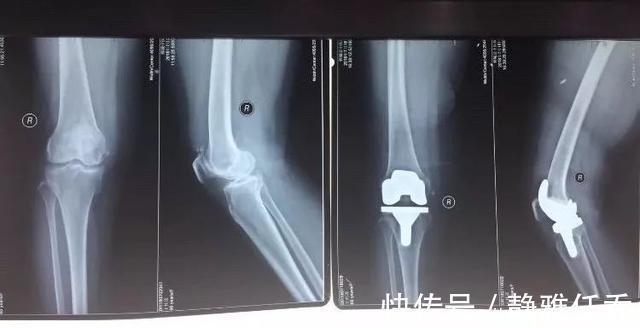

路女士还伴有半月板撕裂清晨刚走路或者长时间走路后疼痛感尤为强烈疼痛评分高达10分相当于女性生孩子时的分娩痛经检查夫妻俩的膝关节均严重变形

在医生的建议性夫妻双方做了膝盖置换手术用人工材料替代膝关节表面软骨